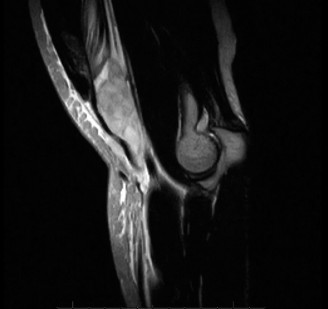

The correct answer is (E). This patient has a suspected distal biceps tendon rupture. He has the classic presentation of an eccentric overload injury along with a pop and pain in the antecubital fossa. However, his examination is inconclusive for complete versus partial tendon tear. The hook test is performed by asking the patient to actively flex the elbow to 90 degrees and fully supinating the forearm (see Fig. 2–119). The examiner then attempts to hook their index finger under the lateral edge of the tendon and palpate a cordlike structure representing the biceps tendon. This test has been shown to be both highly sensitive and specific (up to 100%), but it is inconclusive in this case. An MRI is warranted to assess the integrity of the distal biceps tendon, to distinguish between complete versus partial rupture (Fig. 2–120). This could alter management as the optimal treatment of partial tendon ruptures is not entirely clear. There is relative urgency to doing this, as early surgical intervention after injury is preferred to facilitate primary repair.

Figure 2–119_Figures demonstrating the hook test. (A–C) The patient actively supinates with the elbow flexed 90 degrees. An intact hook test allows the examiner to hook their index finger under the intact biceps tendon from the lateral side. (D–E) With an abnormal hook test, there is no cord-like structure under which to hook a finger. (Reproduced with permission from Sutton KM, Dodds SD, Ahmad CS, Sethi PM. Surgical treatment of distal biceps rupture. _J Am Acad Orthop Surg. 2010 Mar;18(3):139–48.)

Figure 2–120 MRI depicting distal biceps tendon rupture.

What is the most significant strength deficit resulting from nonoperative treatment of a distal biceps tendon injury?

The correct answer is (D). By its anatomic insertion on the radial tuberosity, the biceps brachii serves as both an elbow flexor and supinator of the forearm. There is a greater percentage loss of supination strength as the brachialis serves as the primary elbow flexor. Nesterenko et al. showed that patients with a unilateral biceps rupture lost 37% flexion strength and 46% supination strength. Different reports exist regarding the effect of biceps injury on elbow endurance. Given the functional deficits associated with nonoperative treatment of complete ruptures, conservative treatment is reserved for only low demand or medically infirm patients in these cases.